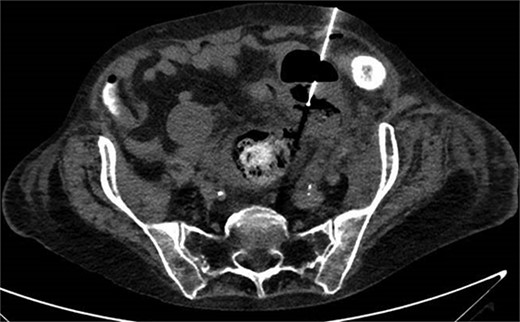

A 65-year-old female with a history of hyperlipidemia, hypertension, hip replacement, lumbar spinal fusion, chronic pain management, and prior laparotomy for endometriosis presented with a 3-day history of nausea, vomiting, and abdominal pain. She had no prior history of diverticulosis or colonoscopy. On examination, she was afebrile and hemodynamically stable. Physical examination revealed left lower quadrant tenderness, swelling, erythema, and fluctuance, suggesting an abdominal wall abscess (Figs 1 and 2). Laboratory tests showed leukocytosis with a count of 24.6 and a positive urinalysis with 2+ leukocytes. A CT scan of the abdomen and pelvis revealed a 3.8 × 3.6 cm air and fluid pocket in the low left anterior abdominal wall, indicative of an abscess likely at the site of a previous drain (Fig. 3). Additionally, there was a 2.8 × 1.8 cm irregular air pocket in the left pelvis, where an abscess had been identified in prior imaging.

CT from readmission with anterior abdominal wall abscess and left pelvic abscess.

One month prior, the patient was admitted for complicated perforated sigmoid diverticulitis. Treatment included piperacillin-tazobactam (Zosyn), bowel rest, and fluid resuscitation. On hospital Day 6, her condition worsened with increased nausea, vomiting, and an elevated WBC count of 15. CT imaging revealed a 4.8 × 4.4 × 4.0 cm diverticular abscess, leading to CT-guided percutaneous drainage by interventional radiology (Figs 4–7). Cultures grew Citrobacter sedlakii and Enterococcus faecium vancomycin resistant Enteroccus (VRE), and treatment was adjusted to include Bactrim, followed by daptomycin and levofloxacin. The abscess resolved after 3 weeks, and the drain was removed before discharge. The patient was instructed to follow up with her surgeon and undergo a 6-week interval colonoscopy.

CT showing resolution of abscess with IR pigtail drain in place.